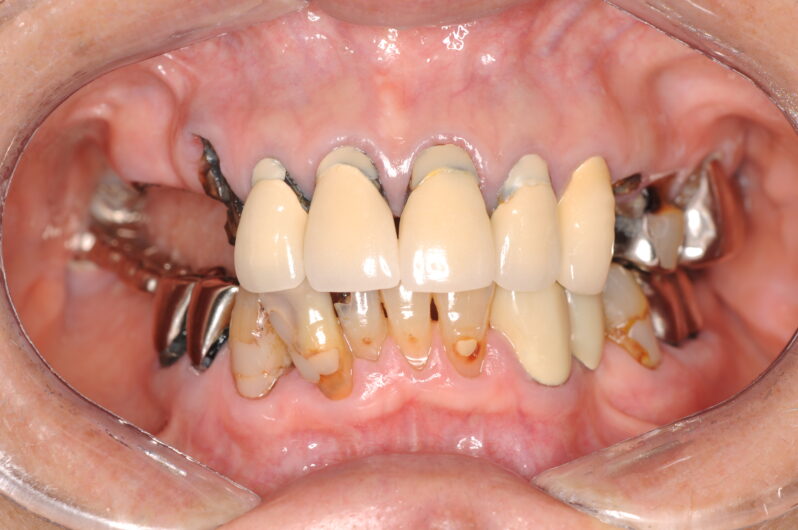

*10年前の写真

先日、10年前にインプラント治療を受けられた患者様から連絡がありました。60代でインプラント治療を開始され、現在は70代になられたこの方は、定期メインテナンスを欠かさず継続されている模範的な患者様です。